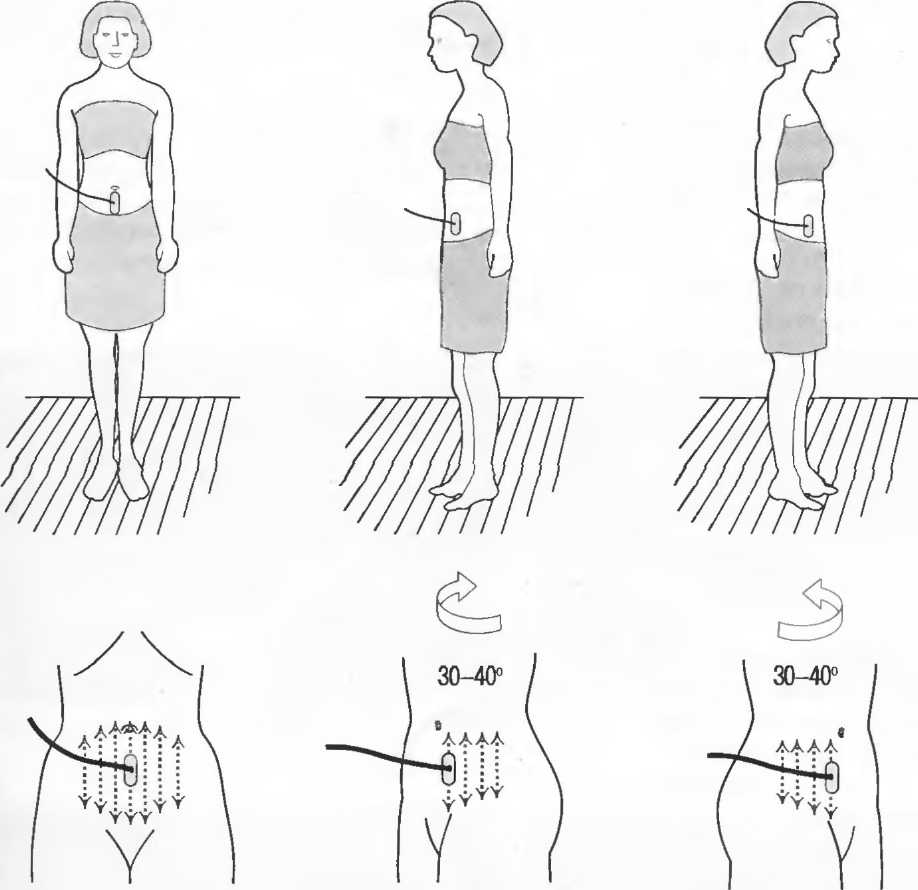

1. Подготовка

Пациент не должен пить и есть в течение 8 ч перед исследованием. Если жидкость необходима для предотвращения дегидратации, можно давать пациенту только воду. При острой симптоматике исследование можно проводить без подготовки. Детям, если позволяют клинические условия, пища и вода не даются в течение 3 ч до исследования.

При более углубленном исследовании, если нет клинических противопоказаний, может быть полезным дополнительный прием воды, особенно при исследовании поджелудочной железы, нижних отделов живота и таза.

2. Положение пациента. Пациент может лежать в удобной позе на спине. Под голову можно положить маленькую подушку, в случае выраженного напряжения передней брюшной стенки подушечку можно поместить также под колени пациента.

Намажьте живот гелем.

Пациенту разрешается дышать спокойно, однако при исследовании отдельных органов требуется задержка дыхания на вдохе.

3. Выбор датчика. Используйте датчик 3,5 МГц для взрослых и датчик 5 МГц для детей и худых взрослых. Предпочтительны конвексные или секторные датчики.

4. Установите правильный уровень общей чувствительности. Начинайте исследования, поместив датчик центрально в верхней части живота под мечевидным отростком и попросите пациента глубоко вдохнуть и задержать дыхание на вдохе.

Поверните датчик направо до того, как начнет визуализироваться печень. Отрегулируйте чувствительность, чтобы изображение имело нормальную однородную зхоструктуру. Должна быть хорошо различима высокоэхогенная линия диафрагмы сразу за задними отделами печени (рис. 27а).

Воротная и печеночные вены должны визуализироваться как трубчатые структуры с анзхогенным просветом. Стенки воротной вены высокозхогенны, но стенки печеночных вен практически не видны (рис. 276).

Рис.27а. Продольный срез. Неизмененная печень и диафрагма.

Рис.27б. Продольный срез: печеночные и воротная вены.

Рис.27в. Поперечный срез через неизмененную печень.

Техника сканирования

После того как вы отрегулировали чувствительность прибора, медленно передвигайте датчик от средней линии вправо, через каждый сантиметр останавливаясь и проверяя изображение. Проверяйте на различных уровнях. После того как вы исследовали правую сторону, таким же образом исследуйте и левую сторону. При этом датчик нужно направлять в различных направлениях, для того чтобы лучше локализовать объект и получить больше информации. Очень важно исследовать всю брюшную полость: если после изменения угла наклона датчика верхняя часть печени или селезенки не визуализируются, необходимо проводить сканирование через межреберные промежутки.

После этих поперечных сканов разверните датчик на 90° и снова начните сканировать от мечевидного отростка. Снова локализуйте печень и при необходимости попросите пациента задержать дыхание на глубоком вдохе, чтобы визуализировать ее лучше. Убедитесь, что уровень чувствительности установлен правильно. При необходимости наклоняйте датчик по направлению к голове пациента. Проводите исследование по межреберным промежуткам.

Ниже ребер держите датчик в вертикальном положении и передвигайте его по направлению к ногам (каудально). Повторите в различных вертикальных плоскостях по всему животу.

Если какая-нибудь часть живота визуализируется плохо, можно проводить исследование в положении больного сидя или стоя. При необходимости проводится исследование в положении пациента на боку с приподнятой головой; чаще зто используется при исследовании почек и селезенки. Не стесняйтесь поворачивать пациента. Если вы заподозрили патологию, используйте технические приемы, описанные в соответствующих разделах.

Важно визуализировать:

|

1. |